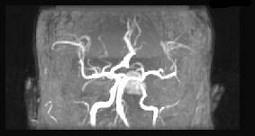

问题 男性,55岁,头痛1年余,2个小时前突然出现剧烈头痛,MRI检查如图所示,最可能的诊断为()

选项 A.垂体瘤 B.脑膜瘤 C.颅咽管瘤 D.垂体瘤并卒中 E.动脉瘤

答案 D